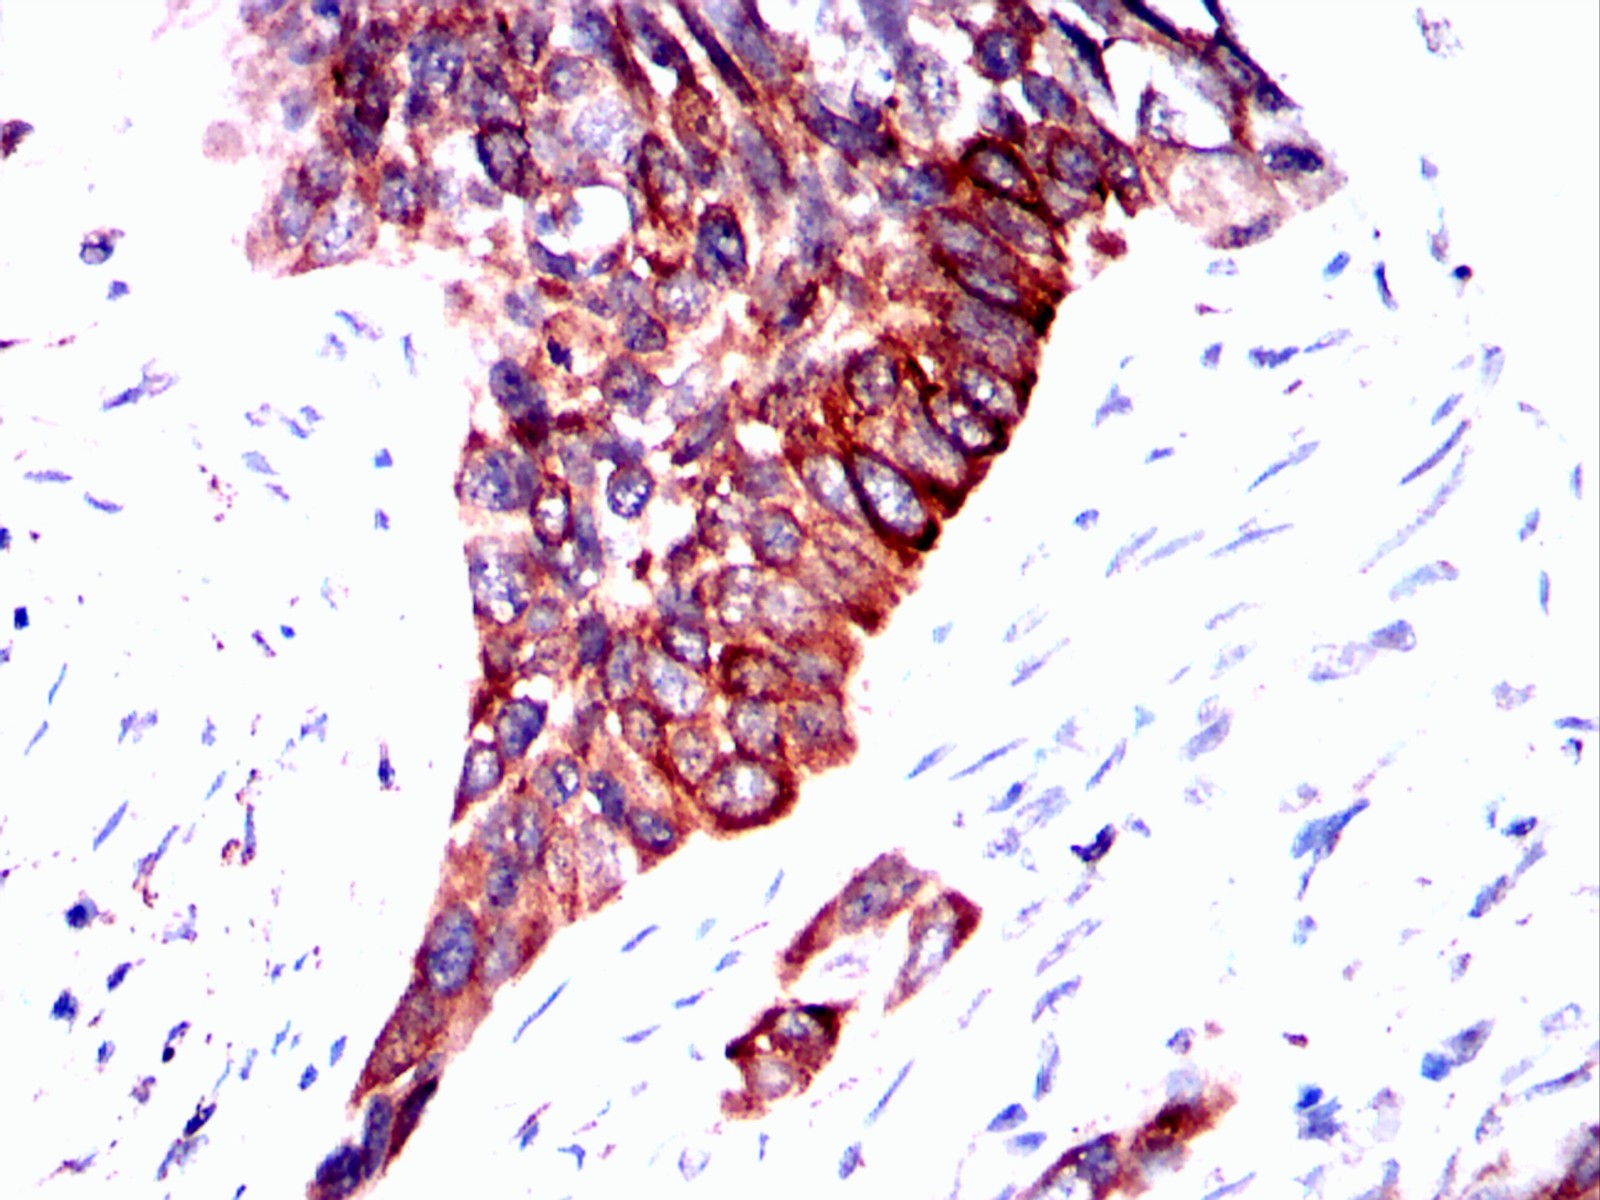

Immunohistochemical analysis of paraffin-embedded esophageal cancer tissues using ERBB3 mouse mAb with DAB staining.

Immunohistochemical analysis of paraffin-embedded esophagus tissues using mouse mAb with DAB staining.